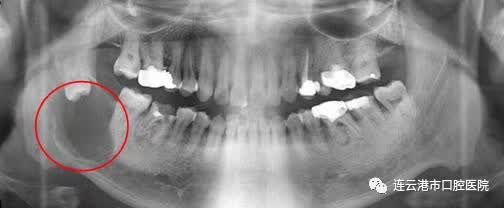

5.智齿已引起下颌骨囊肿或肿瘤